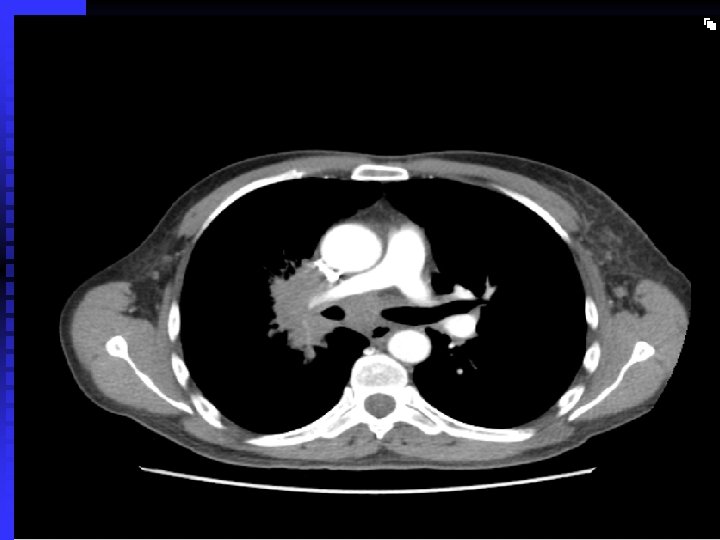

Case 1 50 year old Asian man n 30 pack year history of smoking n Strong family history of malignancy n Persistent cough for > 6 months n Frequent visits to GP: several course of antibiotics n Admitted to St. Helier Hospital with haemoptysis and weight loss n Cervical lymphadenopathy, clubbed n

Case 1 Tumour seen right upper lobe and right intermediate bronchus as Bronchoscopy n Poorly differentiated adenocarcinoma n Referred to RMH: Stage 4 disease, so palliative chemotherapy only n n Early chest X-ray and referral after onset of symptoms may have made a difference !